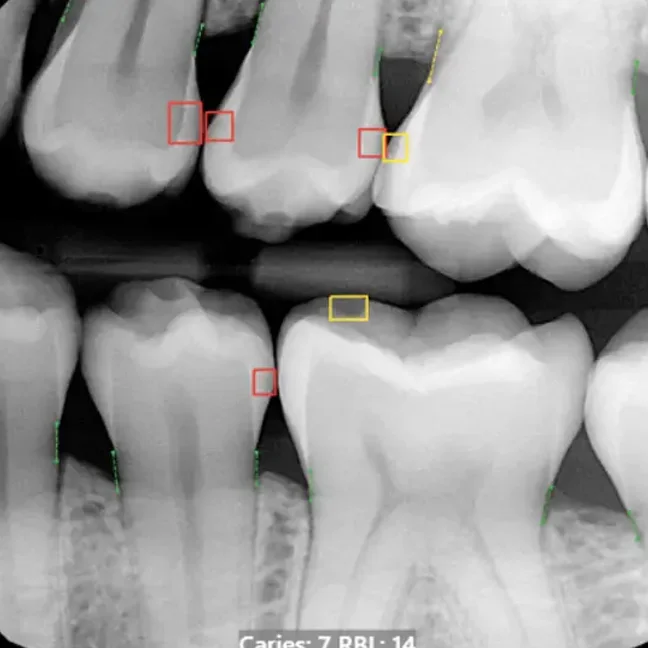

Digital x-rays are safe, quick, and comfortable. Using the latest technology, we can create crisp, high-resolution images of your mouth’s structure, so we can make accurate diagnoses and treatment plans. Digital x-rays use only a fraction of the radiation as traditional film x-rays, so you can rest easy. Most patients receive one or two full sets of x-rays every year, but we may recommend additional imaging in the case of a dental emergency, or if we find an oral health issue that we need to investigate further. And with our CBCT scanner, there’s no more guesswork, only great results.

Our cone beam computed tomography scanner takes dental imaging to the next level by capturing detailed 3D views of your teeth, jawbone, nerves, and surrounding tissues in a single scan. This advanced technology allows our team to plan complex procedures like dental implants with pinpoint precision, identify hidden issues that traditional x-rays might miss, and visualize your entire oral anatomy from every angle. The scan takes just seconds to complete and provides invaluable information that helps us deliver more predictable outcomes and personalized care tailored to your unique needs.